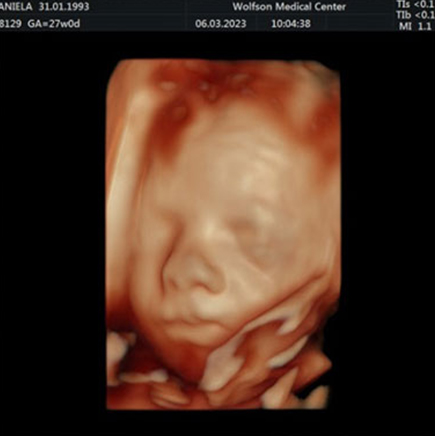

סקירה מערכות מאוחרת

יש לעשות בין השבוע ה־20 לשבוע ה־23 להיריון

סקירת מערכות מאוחרת (שנקראת גם “סקירה שנייה”) היא בדיקת אולטרסאונד הסוקרת את האיברים של העובר במטרה לאתר מומים וממצאים לא תקינים